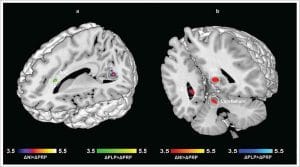

V úlohách rozpoznávania nepríjemných podnetov sa medzi účastníkmi z placebovej alebo kontrolnej skupiny a šťastnejšími účastníkmi zo skupiny s probiotikami prejavil jasný rozdiel – doslova: Funkčná analýza magnetickej rezonancie ukázala, že určité oblasti mozgu boli silnejšie prekrvené, a teda viac aktivované. Konkrétne sa aktivovali oblasti mozgu zodpovedné za výkonnosť pamäte, zlepšenie motorických schopností a vyššiu pozornosť. To sa prejavilo aj v miere rozpoznania: zatiaľ čo kontrolná skupina alebo skupina s placebom rozpoznala menej ako 70 % opätovne zobrazených obrázkov, v skupine s probiotikami bolo rozpoznaných dokonca viac ako 85 % obrázkov.

© Bagga et al. (2018), DOI 10.1080/19490976.2018.1460015